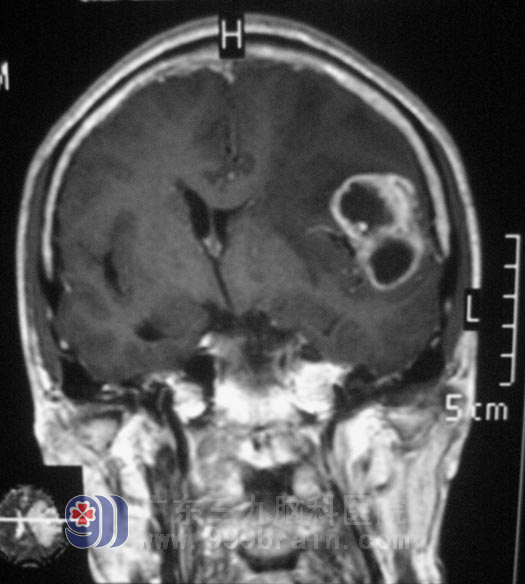

住进广东三九脑科医院综合神经外科后,头颅核磁共振结果提示:左侧额颞叶交界处占位病灶,大小约27mm×36.4mm×41.3mm,初步考虑恶性肿瘤,胶质母细胞瘤可能性大,不排除单发转移瘤;而且伴有大脑镰下疝形成、脑白质散在脱髓鞘灶。

余老伯的肿瘤压迫症状明显,精神食欲差,右下肢肢体乏力,日常生活需要家人协助,经检查排除转移瘤的可能。在完善手术相关准备后,由鲁明主任主刀,在全麻下行“左侧额颞叶肿瘤切除术”,术中见肿瘤呈鱼肉样,额下回局部脑组织水肿明显,肿瘤质地较韧。在显微镜下沿边界全切肿瘤,术后CT显示:余先生颅内压力和脑水肿情况均较术前明显缓解,头痛症状也有所好转。手术后,余先生精神食欲明显好转,脸上的笑容和话语也多了,已经能自行下床活动。术后经病理证实为:(左额颞叶)胶质肉瘤,WHO IV级。余先生还要接受后续的放化疗。